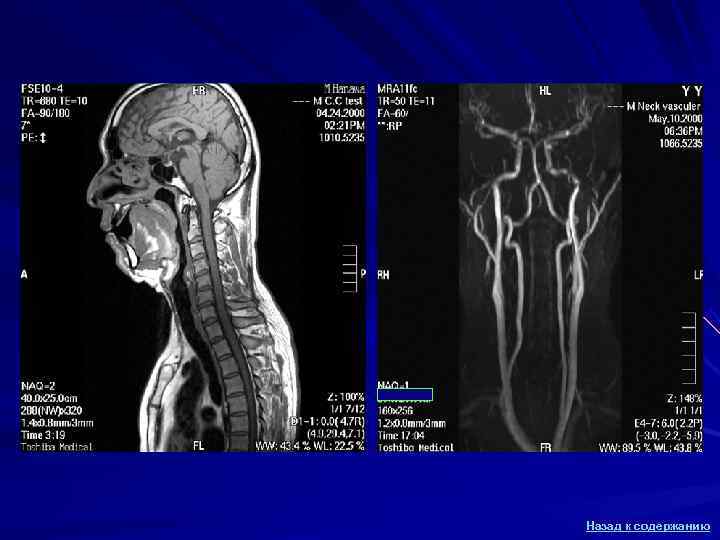

МР-ангиография сосудов шеи Общая Наружная сонная сонная артерия артерия Подключичная артерия Внутренняя сонная артерия Брахио- цефальный ствол Общая Аорта сонная артерия Позвоночные артерии Назад к содержанию

МРТ в неврологии Исторически первым применением МРТ было исследование головного мозга , открывшее новые горизонты в диагностике неврологических заболеваний. МРТ оказалась единственным методом, позволяющим визуализировать бляшки рассеянного склероза и определить наличие активной воспалительной демиелинизации. На сегодняшний день МРТ стала основным методом нейровизуализации, оттеснив на второй план КТ. Применение новых возможностей МРТ позволяет существенно улучшить результаты лечения пациентов с опухолями головного мозга, в том числе за счет определения участка наибольшей злокачественности опухоли для его стереотаксической биопсии, а также неинвазивного моделирования и планирования хирургической операции с сохранением жизненно-важных функций головного мозга. У пациентов с острейшей стадией инсульта МРТ позволяет дифференцировать геморрагические и ишемические поражения, прогнозировать развитие инфаркта мозга и определять показания к тромболитической терапии. У пациентов с микроаденомами гипофиза или интраканаликулярными невриномами вестибулокохлеарного нерва МРТ позволяет выявлять опухоль на ранней стадии развития, задолго до появления КТ-признаков. Назад к содержанию

МРТ шейного отдела позвоночника Продолговатый Мозжечок мозг Первый шейный Второй позвонок шейный позвонок Спинной мозг Тело пятого позвонка Остистый отросток Межпозвонковый диск Назад к содержанию